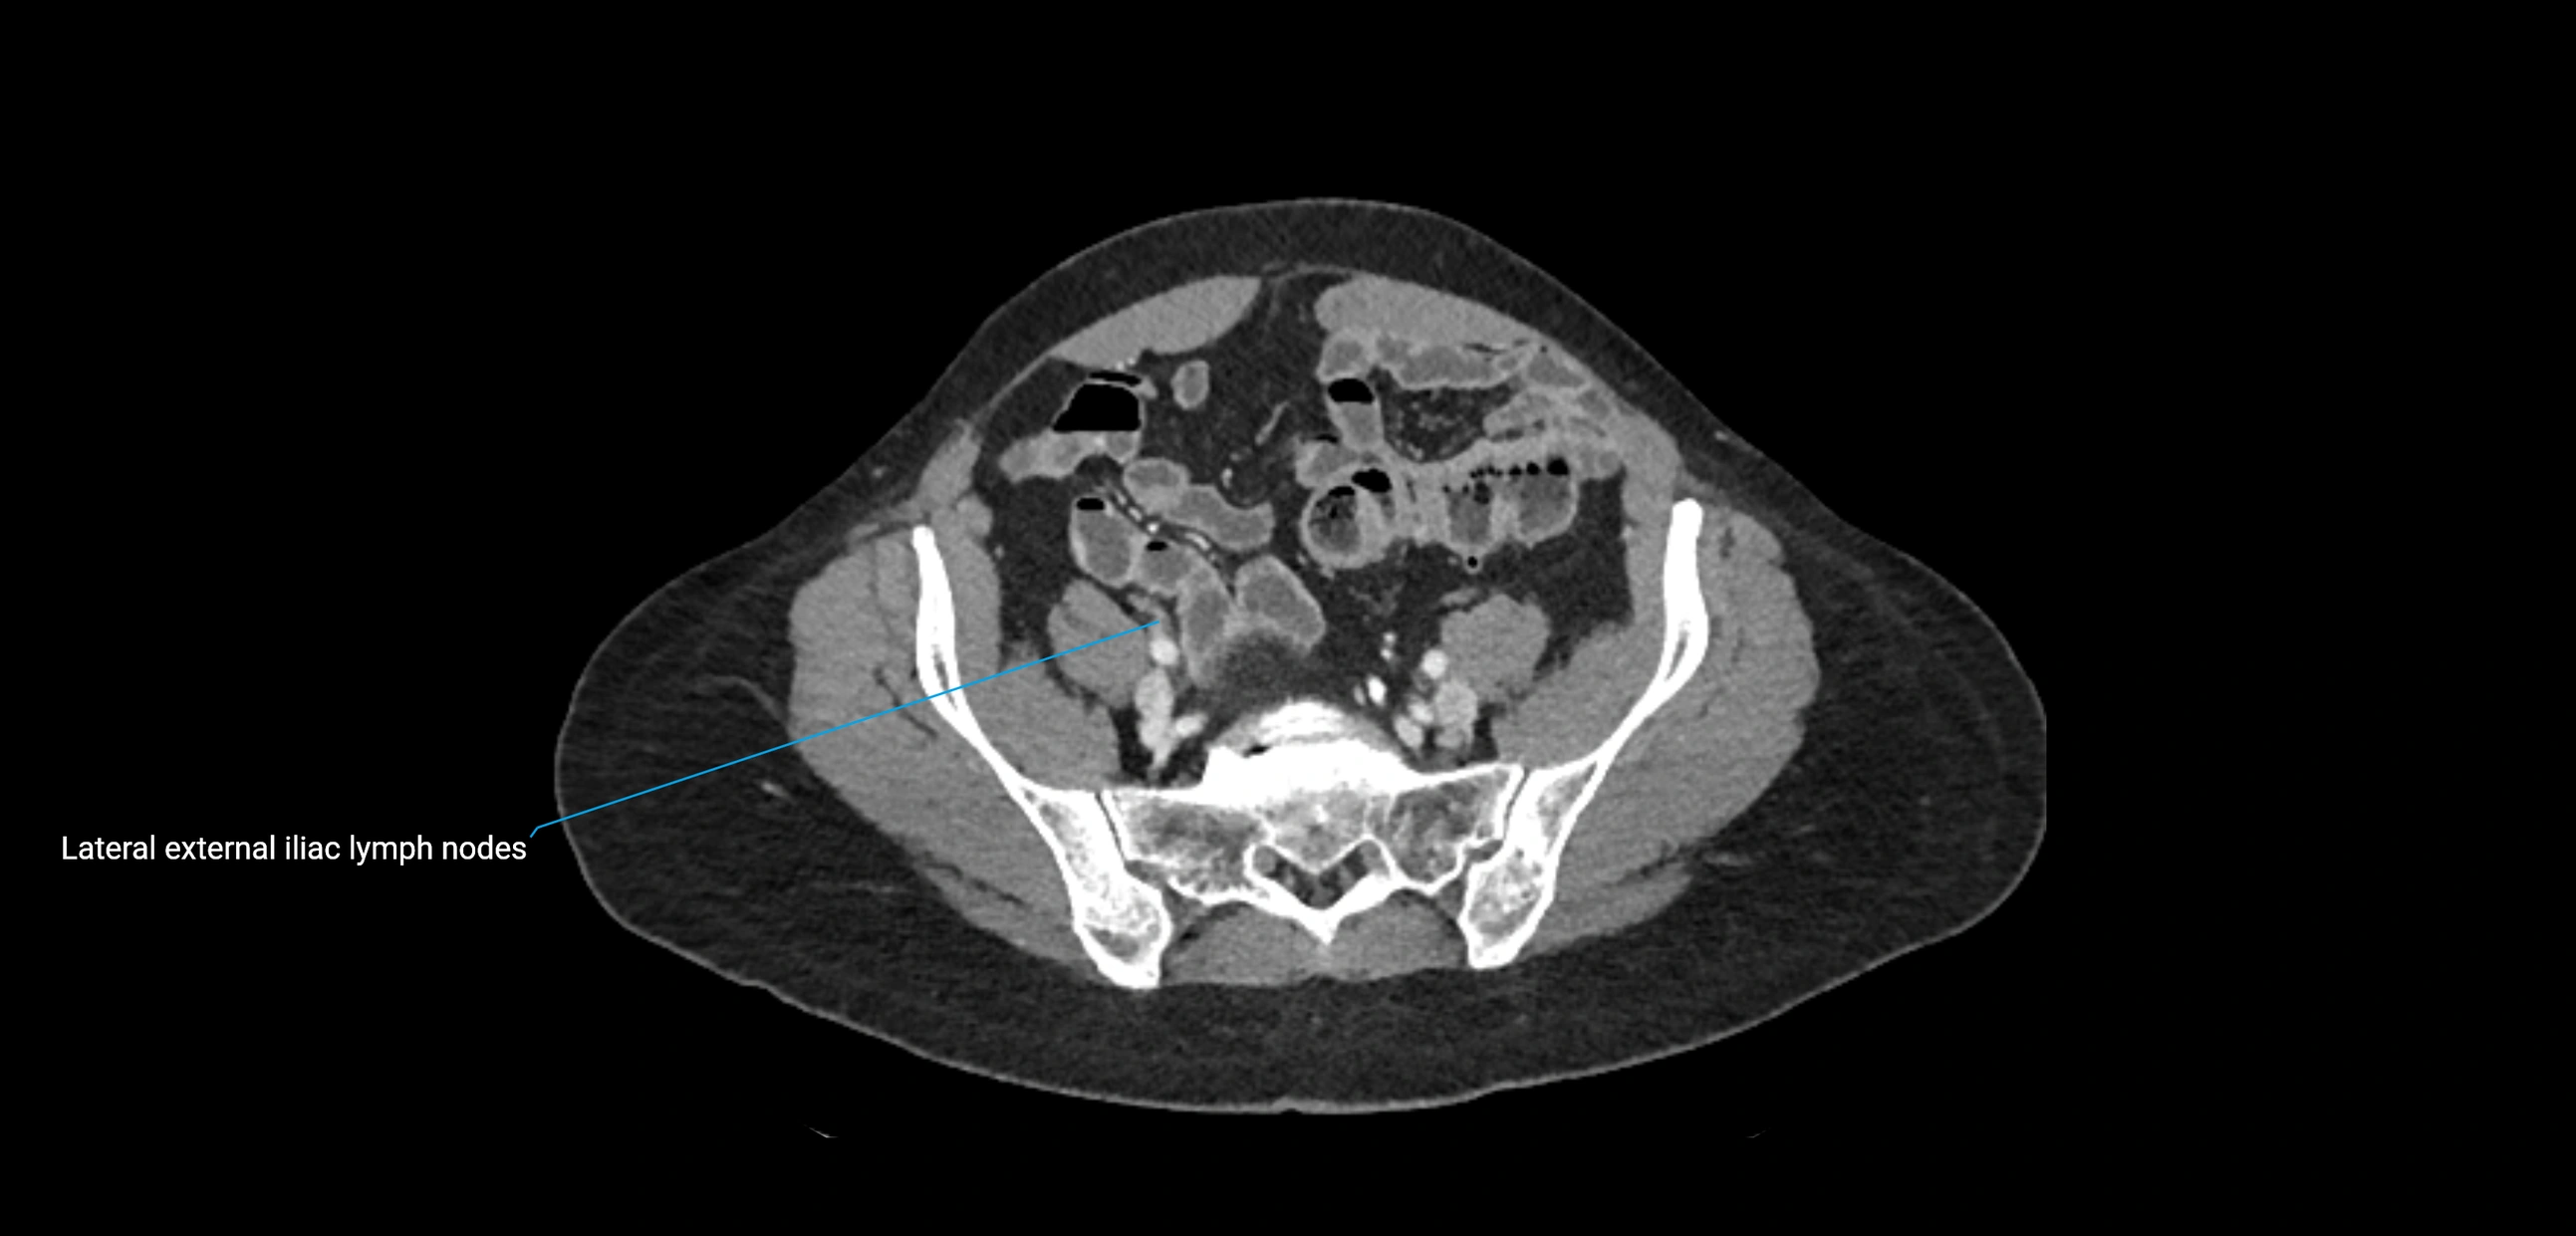

CT Appearance

CT Pre-Contrast:

• Nodes appear as soft-tissue density nodules adjacent to the aorta and IVC

CT Post-Contrast:

• Normal nodes enhance homogeneously

• Malignant nodes may show heterogeneous enhancement, central necrosis, or conglomerate formation

• Size >1 cm short axis is suspicious, though morphology and distribution are equally important

CT Venography (CTV):

• Demonstrates nodal encasement or compression of adjacent vessels (aorta, IVC, renal veins)

• Useful in staging testicular and ovarian malignancies

• Provides 3D reconstructions for retroperitoneal lymph node dissection planning